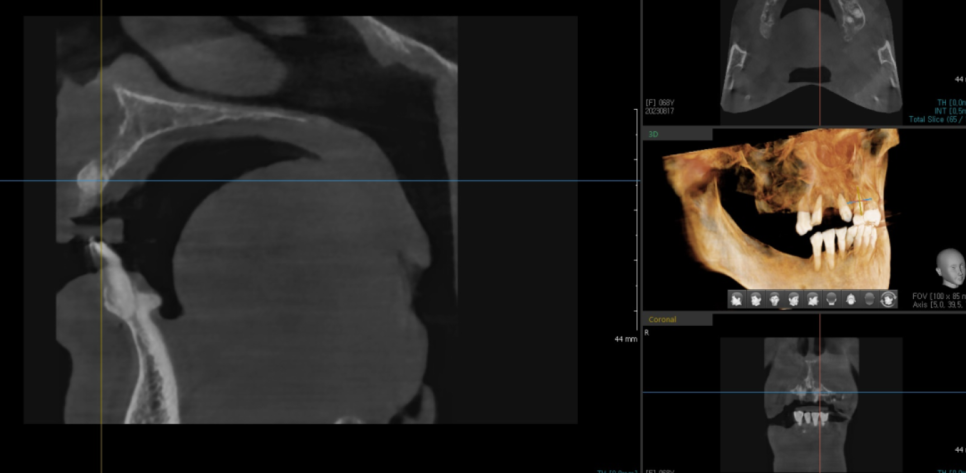

지난 시간에 말씀드린

디지털 임플란트

오늘 환자분도 가이드를 제작

적극적으로 디지털 기술을 활용했습니다.

23.10.10

디지털 기술을 사용하여 가이드를 제작하고

모의 수술을 진행하면

당일 전악 임플란트 수술도 가능합니다.

식립할 임플란트의 사이즈, 두께, 길이

위치까지 분석을 해주니

전악 임플란트 수술 시 요긴하게 사용하고 있습니다.